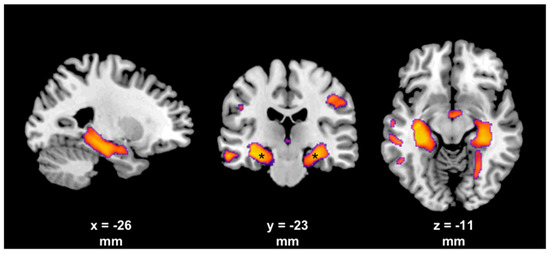

- Ali, S.O.; Thomassen, M.; Schulz, G.M.; Hosey, L.A.; Varga, M.; Ludlow, C.L.; Braun, A.R. Alterations in CNS activity induced by botulinum toxin treatment in spasmodic dysphonia: An H215O PET study. J. Speech Lang. Hear. Res. JSLHR 2006, 49, 1127–1146. [Google Scholar] [CrossRef]

- Nevrlý, M.; Hluštík, P.; Hok, P.; Otruba, P.; Tüdös, Z.; Kaňovský, P. Changes in sensorimotor network activation after botulinum toxin type A injections in patients with cervical dystonia: A functional MRI study. Exp. Brain Res. 2018, 236, 2627–2637. [Google Scholar] [CrossRef]

- Dresel, C.; Bayer, F.; Castrop, F.; Rimpau, C.; Zimmer, C.; Haslinger, B. Botulinum toxin modulates basal ganglia but not deficient somatosensory activation in orofacial dystonia. Mov. Disord. 2011, 26, 1496–1502. [Google Scholar] [CrossRef] [PubMed]

- Dresel, C.; Haslinger, B.; Castrop, F.; Wohlschlaeger, A.M.; Ceballos-Baumann, A.O. Silent event-related fMRI reveals deficient motor and enhanced somatosensory activation in orofacial dystonia. Brain 2006, 129, 36–46. [Google Scholar] [CrossRef] [PubMed]

- Opavský, R.; Hluštík, P.; Otruba, P.; Kaňovský, P. Sensorimotor network in cervical dystonia and the effect of botulinum toxin treatment: A functional MRI study. J. Neurol. Sci. 2011, 306, 71–75. [Google Scholar] [CrossRef] [PubMed]

- Opavský, R.; Hluštík, P.; Otruba, P.; Kaňovský, P. Somatosensory cortical activation in cervical dystonia and its modulation with botulinum toxin: An fMRI study. Int. J. Neurosci. 2012, 122, 45–52. [Google Scholar] [CrossRef]

- Delnooz, C.C.S.; Pasman, J.W.; Beckmann, C.F.; van de Warrenburg, B.P.C. Task-free functional MRI in cervical dystonia reveals multi-network changes that partially normalize with botulinum toxin. PLoS ONE 2013, 8, e62877. [Google Scholar] [CrossRef] [PubMed]